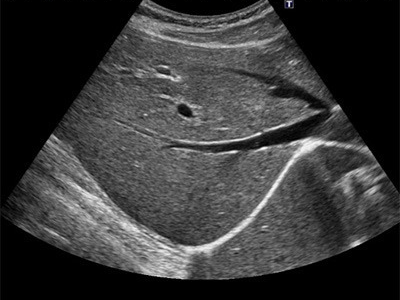

담낭 및 담도계 질환

- 담낭결석(담석증): 담낭 내 결석 존재 여부, 크기, 위치 확인

- 담낭염: 담낭 벽의 두께 증가, 액체 저류 관찰 가능

- 담도 폐쇄 및 담관암: 담관 확장 여부 및 폐쇄 병변 확인